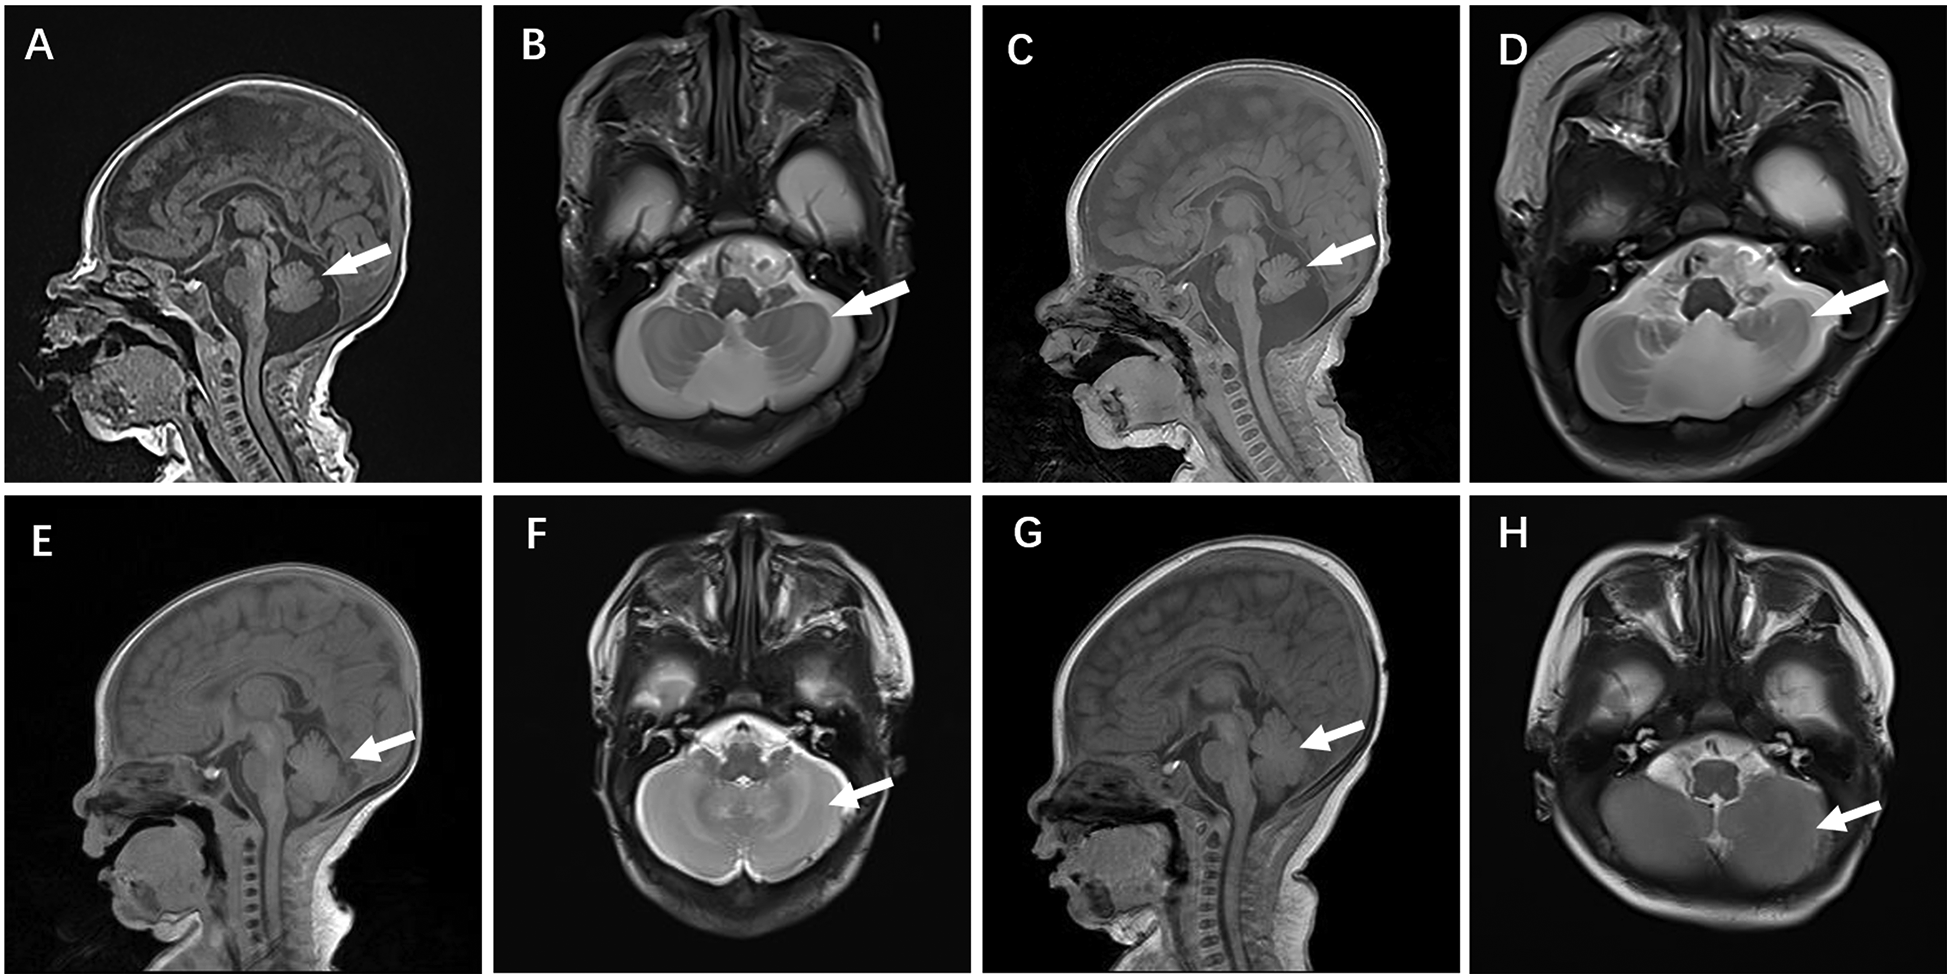

Figure 4

Cranial MR images of case 4 brain MR Images of the 2-week-old showed cerebellar hypoplasia on (A) (T1WI) and (B) (T2WI) images. At 2 months, (C) (T1WI) and (D) (T2WI) images of the same level showed aggravated cerebellar dysplasia. (E–H) displayed a normal skull image of the same age and sex, with the arrows indicating the cerebellum.

Case 4 was administered oral coenzyme Q10 treatment at four weeks of age, as detailed in Table 2. Throughout the treatment period, the patient underwent periodic brain MRI scans, EEG tests, and assessments of plasma coenzyme Q10 concentration. Initial brain imaging did not reveal any significant changes. However, after two months, Compared to boys his age, MRI scans indicated a more pronounced cerebellar dysplasia in the coronal T1-weighted and sagittal T2-weighted images, despite the coenzyme Q10 administration (Figure 4). The EEG showed epileptic wave ranging from localized to generalized. Phenobarbital has exhibited favorable results in treating neonatal seizures. During a stable phase, Case 4 contracted rotavirus, leading to a deterioration in the patient's condition, including respiratory failure, reduced myocardial contractility, and severe lactic acidosis (with normal lactic acid levels prior to the infection, but severe hyperlactacemia during the rotavirus episode). Interventions such as respiratory and circulatory support, along with an increased dosage of coenzyme Q10 (50 mg/kg), successfully reversed the fatal respiratory and circulatory failure, restoring lactic acid levels to normal. Plasma coenzyme Q10 concentrations were monitored throughout the treatment period, ranging from 1.52 to 4.91 umol/L (Reference value range is 0.46–1.85 umol/L). A decrease in concentration (1.65 umol/L) was noted during symptom exacerbation, followed by an increase (8.45 umol/L) after supplementation, leading to symptomatic improvement.